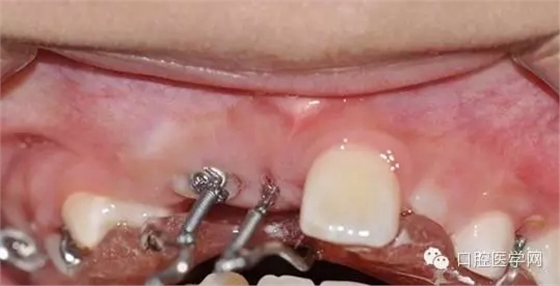

切開:

去除部分礙事牙囊,充分暴漏牙冠便于粘結正畸附件,并用大量腎上腺素壓迫止血。

酸蝕后